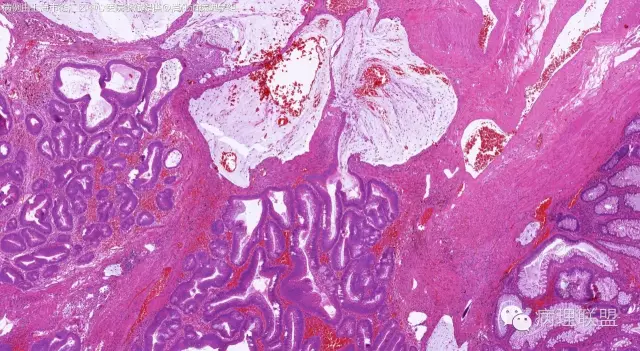

男,64岁,距肛门口45cm息肉大体:灰白结节2*2*1cm(病例由上海市徐汇区中心医院 李斌 提供,致谢!)

管状~绒毛状腺瘤伴低级别上皮内瘤变,黏膜下层部分腺体破裂黏液外溢伴黏液糊形成。

本例部分腺体异位到黏膜下层。

@李斌 李大夫的片子一向漂亮,有赏心悦目的感觉,必须赞一个。这例同意周大夫的意见,低级别绒毛管状腺瘤伴腺体破裂导致的黏液外溢。粘液池周围可见血管扩张淤血、含铁血黄素沉积、肉芽组织形成,提示发生过蒂扭转和出血,这常是造成假浸润、粘液溢出的原因。比较大的绒毛管状腺瘤会有分叶结构,会有比较粗大的平滑肌干,但缺少P-J息肉叶脉样从主干再分支出来的细平滑肌束。作为错构瘤性息肉的一种,P-J息肉的腺体可以分支、扩张、腺腔不规则,但没有细胞异型性,伴发异型增生时,局部出现细胞异型性但不会像这例这样齐刷刷都是异型的腺体。